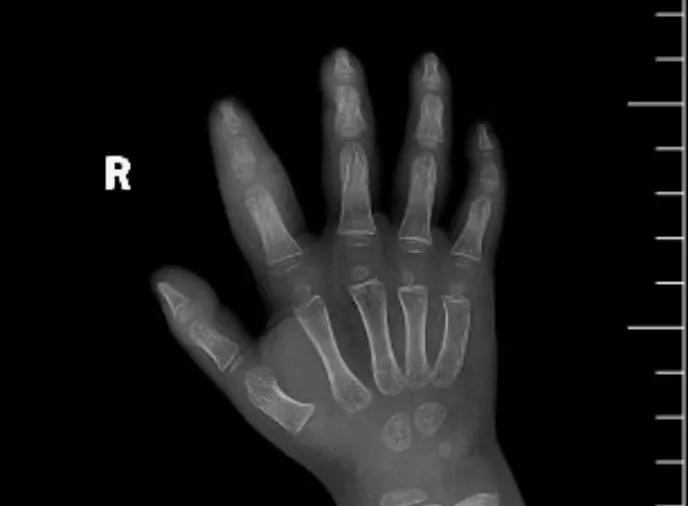

近日,市二院顯微外科接診一名3歲半的小患者,被玉米葉割傷右食指,因家長疏忽大意,導(dǎo)致一個小小的傷口竟然發(fā)展成了骨髓炎。來院時患兒右食指腫脹明顯,既不能伸也不能彎,皮膚發(fā)燙,疼得哇哇大哭。

第三天開始,月月哭鬧不止,一直說手疼,怎么哄也不行,于是在當(dāng)?shù)蒯t(yī)院治療了10來天,然而月月的手指依然腫得像個胡蘿卜,疼痛感依然存在。此時,月月的媽媽才覺得事情不大對勁,于是經(jīng)過打聽,慕名來到市二院顯微外科。入院后,經(jīng)檢查發(fā)現(xiàn),月月的右食指骨質(zhì)有侵蝕,骨骺有缺損,甚至?xí)绊懸院笫种傅陌l(fā)育。聽到這個消息,月月媽媽感覺心都揪住了。